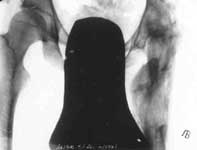

1.Дефект головки и шейки бедра после операции.

2.Открытый артродез тазобедренного сустава с одновременным удлиннением бедра.